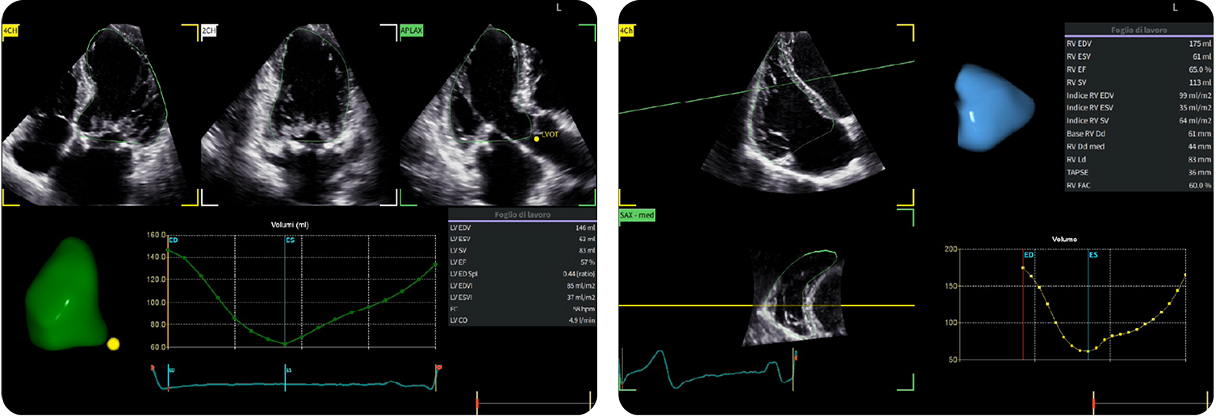

Fifty shades of grey

Caso condiviso da Marcello De Santis